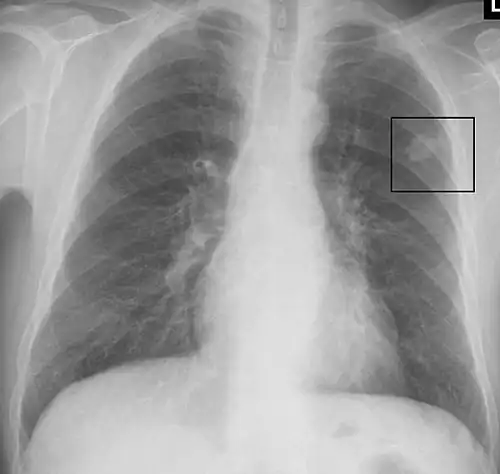

Most cancers are initially recognized either because of the appearance of signs or symptoms or through screening.[125] Neither of these leads to a definitive diagnosis, which requires the examination of a tissue sample by a pathologist.[126] People with suspected cancer are investigated with medical tests. These commonly include blood tests, X-rays, (contrast) CT scans and endoscopy.

The tissue diagnosis from the biopsy indicates the type of cell that is proliferating, its histological grade, genetic abnormalities and other features. Together, this information is useful to evaluate the prognosis and to choose the best treatment.

Cytogenetics and immunohistochemistry are other types of tissue tests. These tests provide information about molecular changes (such as mutations, fusion genes and numerical chromosome changes) and may thus also indicate the prognosis and best treatment.